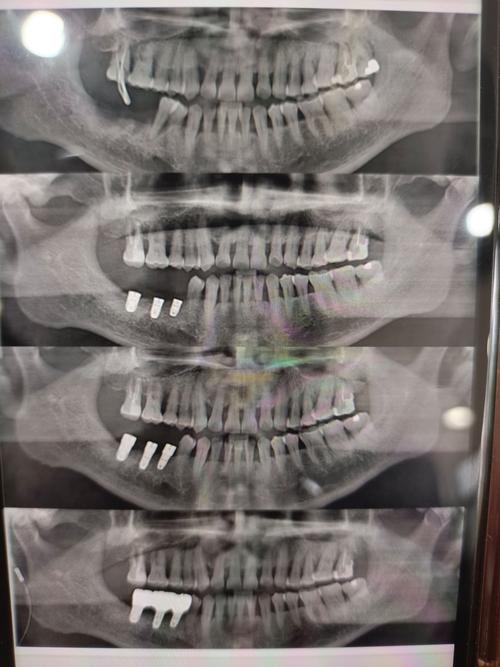

种牙CT检查首选锥形束CT(CBCT),而非传统螺旋CT,CBCT具有辐射剂量低(仅为螺旋CT的1/10-1/100)、空间分辨率高(可达0.1mm)、扫描时间短(10-30秒)等优势,且能三维重建牙槽骨、邻牙、神经血管等结构,为种植体植入位置、角度、深度提供精确数据,普通螺旋CT因辐射剂量高、层厚较厚(通常1-5mm),难以清晰显示牙槽骨的细微骨纹理和重要解剖标志,仅适用于复杂病例的补充检查(如颌骨肿瘤、严重骨缺损)。

CBCT扫描参数需根据患者口腔情况和种植区域个体化调整,核心参数包括扫描视野(FOV)、层厚/分辨率、曝光参数及重建算法,直接影响图像清晰度和诊断价值。

扫描视野(FOV):FOV范围需覆盖目标种植区及周围关键解剖结构,避免遗漏重要信息。

- 小FOV(如5cm×5cm):适用于单颗牙种植,聚焦于目标牙槽骨,可减少辐射剂量,提高局部分辨率。

- 中FOV(如8cm×8cm):适用于多颗连续牙种植,需包含邻牙、牙槽骨及部分颌骨(如下颌骨体部、上颌窦底部)。

- 大FOV(如15cm×15cm或全牙列):适用于全口种植、骨量评估复杂病例(如颌骨萎缩、需植骨者),需包含双侧颞下颌关节、上颌窦、下牙槽神经管等结构。